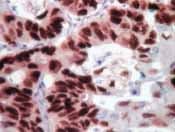

Streptavidin HRP (ready-to-use) is a Streptomyces avidinii protein and suitable for IHC-P.

Applications IHC-P